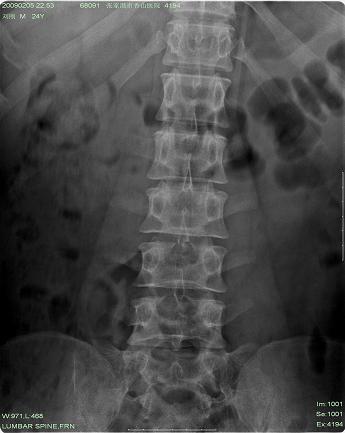

以下是引用hhcckk在2009-3-11 15:43:00的发言:[br]3、4、5腰椎及骶1椎体前上缘不规则,椎间隙改变不明显,结合患者年龄轻考虑:脊椎骨软骨病可能性大[br][br]脊椎骨软骨病又称青年性驼背(scheuerman)。[br][br]1964年sorenson首先提出x线影像学诊断标准:胸段脊柱至少3个相邻椎体有5°或5°以上楔形改变。椎体的楔形变是scheuermann病的基本特点,还可以有其它一些特征,如椎间隙变窄、schmorl结节、椎体终板变窄、不规则或扁平,顶椎前后径增长。

以下是引用随光逐影在2009-3-11 14:43:00的发言:[br]平片:l3、4、5及s1前上缘见类似“切角征”。[br]ct扫描:腰椎多个节段椎间盘向椎体内(椎体前部)突出。